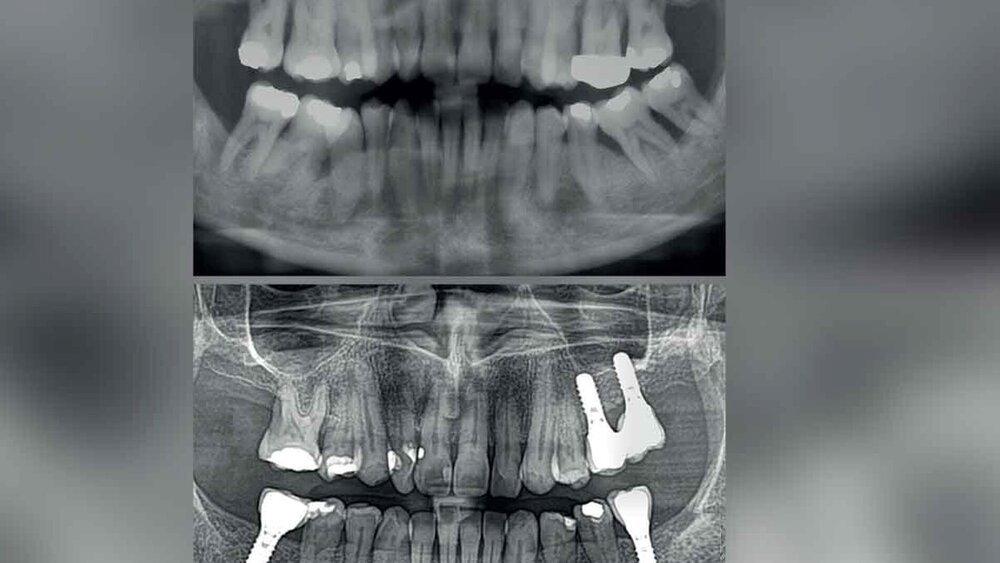

Langzeitdaten sind insbesondere bei Patienten mit der Vorgeschichte einer Parodontitis von großem Interesse, da diese aktuellen Analysen zufolge ein zweifach höheres Risiko für Implantatverlust im Vergleich zu Nicht-Parodontitis-Patienten haben [Carra et al., 2021]. Ziel der vorliegenden prospektiven Studie war es, die klinischen 20-Jahres-Ergebnisse von Implantaten in teilbezahnten Patienten, die zuvor wegen einer Parodontitis behandelt worden waren, und bei parodontal gesunden Patienten zu ermitteln.

Die ursprüngliche Studienpopulation bestand aus 149 teilbezahnten Patienten, die in einer parodontologischen Spezialistenpraxis mit insgesamt 297 Implantaten (SLA, Tissue Level) versorgt worden waren. Diese waren in drei Gruppen unterteilt: parodontal gesunde Patienten (PHP), mäßig parodontal kompromittierte Patienten (mPCP) und schwer parodontal kompromittierte Patienten (sPCP). Nach dem erfolgreichen Abschluss der Parodontal-/Implantattherapie wurden die Patienten in ein individualisiertes Programm der unterstützenden Parodontaltherapie (UPT) aufgenommen. Die Diagnose und Behandlung biologischer Komplikationen (Mukositis und Periimplantitis), die während der UPT auftraten, erfolgte nach dem CIST-Protokoll unter dem Einsatz von Antibiotika beziehungsweise chirurgischer Maßnahmen. Nach zehn Jahren konnten 123 Patienten mit 246 Implantaten und nach 20 Jahren 84 Patienten (22 PHP, 29 mPCP, 33 sPCP) mit 172 Implantaten (39 PHP, 59 mPCP, 71 sPCP) erneut untersucht werden.

Während der Beobachtungszeit wurden zwölf Implantate entfernt (elf aufgrund einer fortgeschrittenen Periimplantitis und eins aufgrund einer Implantatfraktur), was zu einer Gesamtüberlebensrate der Implantate von 93 Prozent führt (94,9 Prozent für PHP, 91,8 Prozent für mPCP und 93,1 Prozent für sPCP [p = 0.29]). Nach 20 Jahren hatten die Patienten der Parodontitisgruppen, die sich adhärent mit der UPT verhalten hatten, keine signifikant höhere Wahrscheinlichkeit eines Implantatverlusts als parodontal gesunde Patienten, die regelmäßig an der UPT teilgenommen hatten. Umgekehrt hatten Parodontitispatienten mit schlechter/keiner Adhärenz zur UPT ein stark erhöhtes Risiko für Implantatverluste (Odds Ratio von 14,59).

Über 20 Jahre hinweg war die Zahl der Patienten, bei denen eine CIST(C/D)-Therapie aufgrund biologischer Komplikationen erforderlich war, in der Gruppe der parodontal Gesunden mit 33,3 Prozent statistisch signifikant niedriger als in den Parodontitisgruppen (mPCP: 48,3 Prozent und sPCP: 61,3 Prozent). Darüber hinaus war nach 20 Jahren das Auftreten von Stellen mit röntgenologischem Knochenabbau von ≥ 3 mm in den Gruppen mPCP (33,33 Prozent) und sPCP (35,15 Prozent) statistisch signifikant höher als in der PHP-Gruppe (17,94 Prozent). Die mittlere Anzahl der während der UPT verlorenen Zähne betrug 0,6 ± 1,0 für PHP, 1,3 ± 1,3 für mPCP bzw. 1,9 ± 1,9 für sPCP.